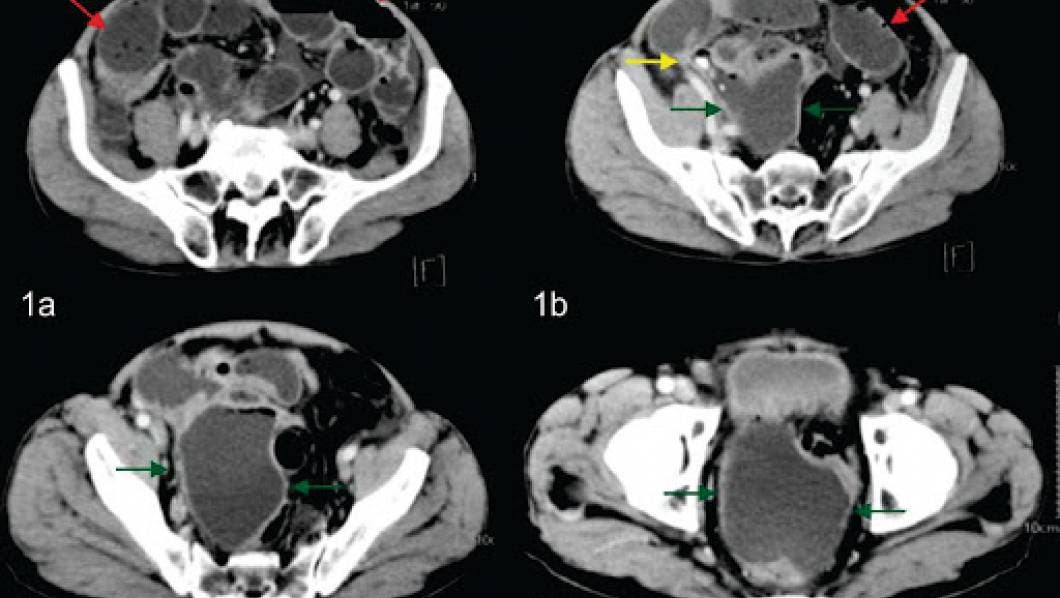

Por su parte la tomografía computada tiene una sensibilidad cercana al 98% y una especificidad que bordea el 100%, permitiendo al radiólogo confirmar este diagnóstico y poder realizar además diversos diagnósticos diferenciales.